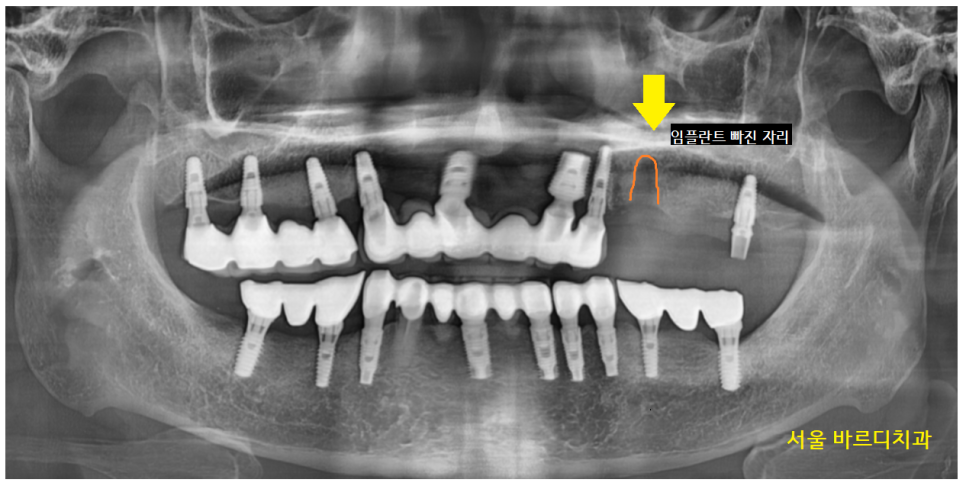

왼쪽 위에 부분을 자세히 보는 x-ray를 촬영해 보았습니다.

23.06.15

임플란트 사이와 사이에 공간이 생겨

음식물이 끼고

잇몸이 부었습니다.

23.07.11

x-ray로 보면 이렇게 생겼습니다.

남은 임플란트 1개는 상태가 괜찮아

그대로 쓰시기로 하고

임플란트가 빠진 곳에 치료 계획을 다시 잡아드렸습니다.